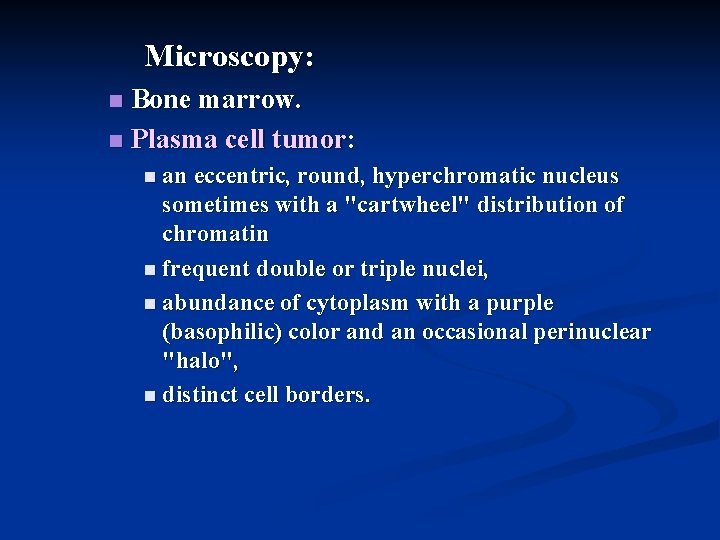

Microscopy: Bone marrow. n Plasma cell tumor: n n an eccentric, round, hyperchromatic nucleus sometimes with a "cartwheel" distribution of chromatin n frequent double or triple nuclei, n abundance of cytoplasm with a purple (basophilic) color and an occasional perinuclear "halo", n distinct cell borders.